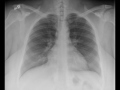

Normal Chest PA and Lateral

Normal chest PA and lateral. The lungs are well inflated. The cardiothymic silhouette is normal. Pulmonary artery branches and airway are normal. Besides obesity, the x-ray is unremarkable.